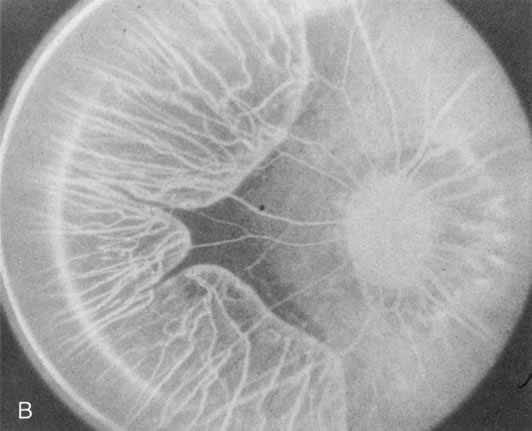

Of more clinical importance is the role of FA in the diagnosis and treatment of cystoid macular edema (CME) (Fig. 1C and D). Stereoscopic FA indicates that the leakage, which may be diffuse or have the typical petaloid stellate appearance of CME, can come from the perifoveal retinal capillaries, from the choroid through the RPE, or from a combination of both sources.4 With the recent suggestion that CME in RP may be successfully treated with acetazolamide,5, 6 FA is thus important to document the diagnosis of CME, establish the origin(s) of leakage, and follow patients during and after therapy.